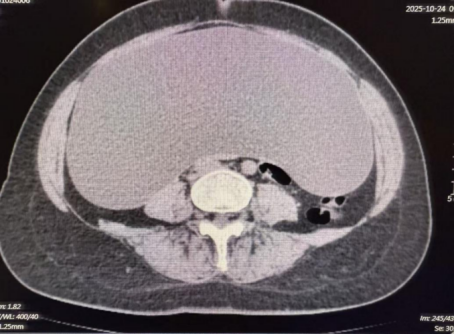

腹腔镜下切除巨大囊肿

一位发现腹腔中出现巨大占位性病变的患者来院就诊,经影像学检查发展腹腔内囊性低密度阴影面积高达45cm×35cm×14cm,对周围脏器形成严重压迫,手术难度极高。王兆太主任团队经周密讨论,决定采用腹腔镜微创技术治疗。术中,团队先分阶段穿刺引流7500毫升囊内液体,为操作创造空间,随后发现囊肿与右侧卵巢、圆韧带关系密切,立即启动多学科协作,邀请妇科范桂芬主任现场指导,精准分离粘连组织、保护重要结构。手术顺利完成,囊肿被完整切除,术中出血量少,患者术后生命体征平稳,快速康复。